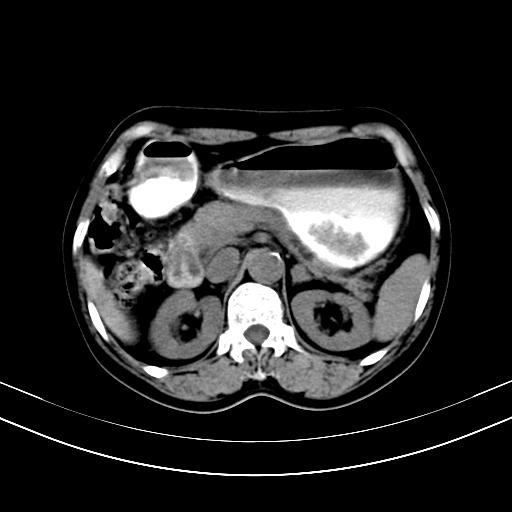

标题: CT12767:肝脏病变请会诊

补充强化片

胃内见充盈缺损,建议行胃镜病理检查,如果胃内无占位,则肝内考虑左叶、尾叶为包膜型肝癌,如有则考虑为转移瘤

胃内的充盈缺损,当时让患者俯卧位在扫描一下就 好了,当然最好是增强扫描,肝脏的病灶平扫很难定性,可以考虑是肝癌·血管瘤·转移瘤!

胃内见充盈缺损,建议行胃镜病理检查,如果胃内无占位,则肝内考虑左叶、尾叶为包膜型肝癌,如有则考虑为转移瘤,左侧肾上腺 明显增大,成结节改变,本人考虑转移瘤可能性大。

胃内的充盈缺损因胃壁不厚,我个人考虑为胃内残留物。肝左叶及尾叶病灶,我首先考虑血管瘤,其次为肝癌。(尾叶的更低密度区太规整)

肝脏左叶和尾叶均见略低密度影,尾叶病变内见坏死?其边界清晰,形态规整1血管瘤,2肝癌待排

胆囊内见一略高密度影,息肉?

1.肝左叶及尾叶占位建议增强2.肝硬化

肝脏左叶和尾叶均见略低密度影,尾叶病变内见坏死?其边界清晰,形态规整1血管瘤,2肝癌待排3建议增强。

胃内充盈缺损考虑为胃内存留物,肝左叶和尾状叶两个病灶,均为低密度,建议增强。

考虑:胃体小弯侧胃癌(或平滑肌瘤恶化或平滑肌肉瘤)伴肝转移,左侧肾上腺转移不除外.

胃内充盈缺损考虑为肿瘤,肝尾叶及左叶肿块考虑转移瘤

胃癌肝内转移及肾上腺转移。

胃窦部占位伴肝及左肾上腺转移可能大,建议增强扫描。

肝脏左叶和尾叶均见略低密度影,尾叶病变内见坏死?其边界清晰,形态规整1血管瘤,2肝癌待排3建议增强或结合临床及超声与实验室检查

肝左叶及尾叶低密度灶,增强有渐进性明显强化,考虑血管瘤。胃内“充缺”首先要排除异物(食物),变换体位可鉴别。增强时机抓的不好,还应该有延时像。

谢谢楼主的增强片子,平扫没发现左侧肾上腺的问题很不好意思,可惜片子只有门脉期,所以还只有猜,肝脏的病灶在门脉期部分强化,首先考虑为血管瘤(其他的用一种病不好解释)胃要喝水就好了现在不好说是否有问题,左肾上腺的问题考虑是肿瘤。

做了增强后,可以明确胃是没有肿瘤的,肾上腺也没有肿瘤.肝左叶的病灶首先考虑血管瘤,应该再延迟,肝尾状叶的病灶仍不能排除肝癌的可能性.